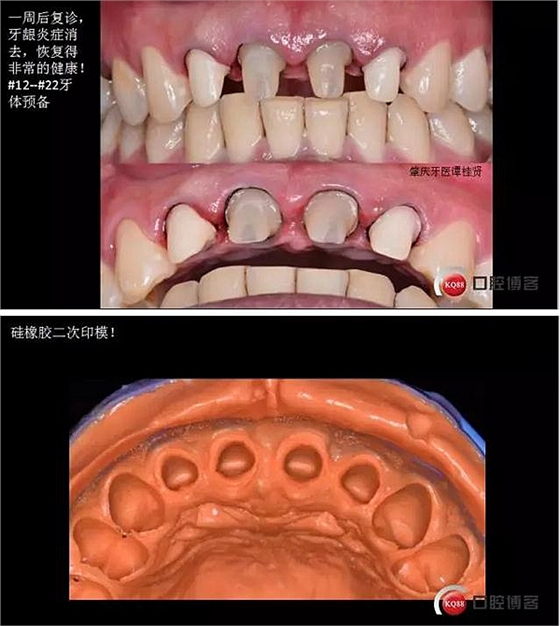

四診(一周后)

五診(又過了一周)

六診(一周后)牙冠做好啦!